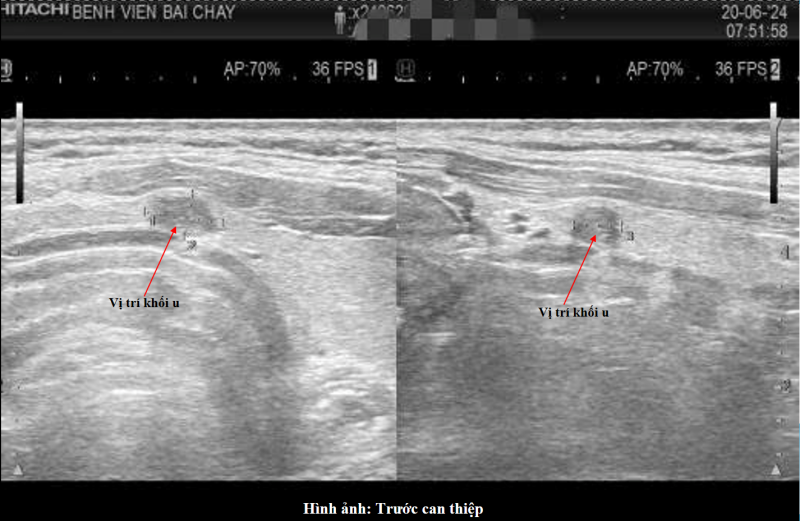

Điển hình là bệnh nhân là L.Đ.H 46 tuổi, trú tại phường Việt Hưng, Quảng Ninh, được phát hiện có nhân tuyến giáp trong quá trình khám sức khỏe. Qua thăm khám lâm sàng, siêu âm và chọc hút tế bào bằng kim nhỏ (FNA), các bác sĩ chẩn đoán bệnh nhân mắc ung thư biểu mô tuyến giáp thể nhú, khối u có kích thước nhỏ dưới 10mm, chưa xâm lấn và chưa ghi nhận di căn hạch.

Hình ảnh siêu âm trước can thiệp.